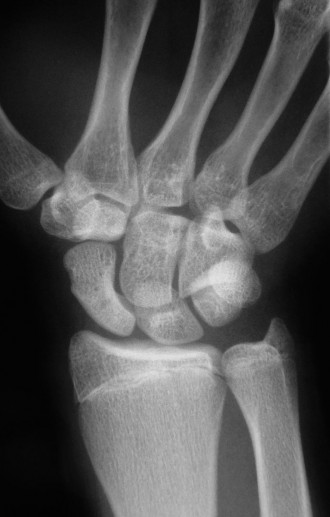

CASE 1 A 14-year-old patient presents with pain in the wrist after a fall. Examination reveals tenderness ove…